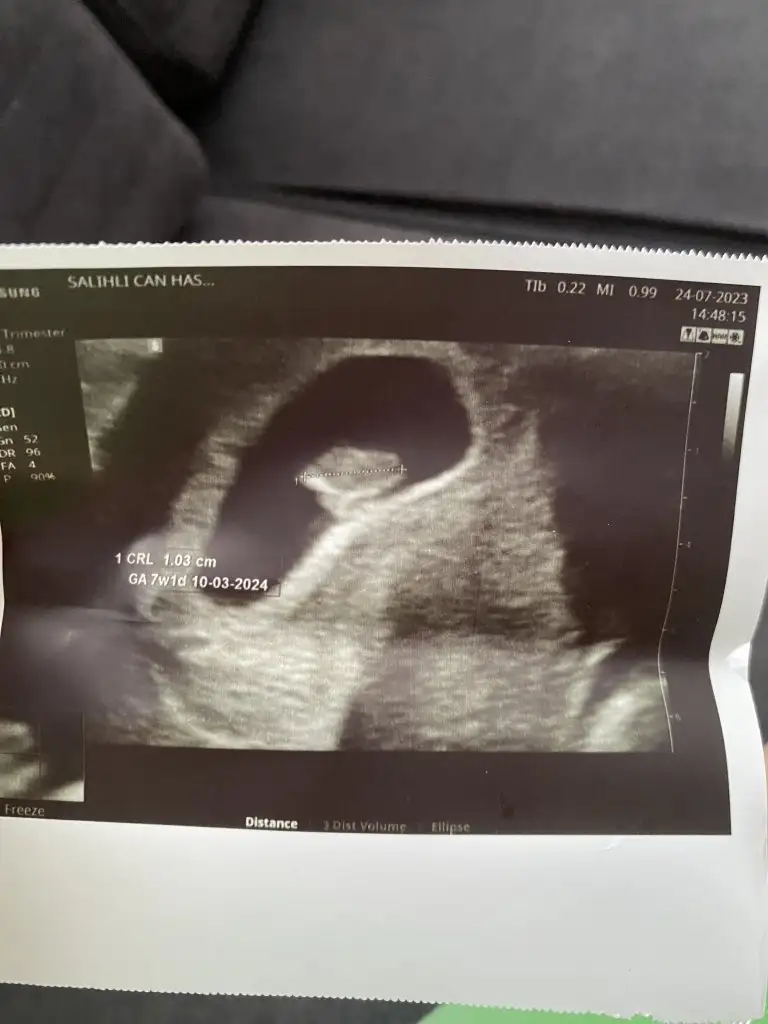

7+3 sizce nedir

Eklentiler

• D6E5FFD5-AEC8-4C19-BCB2-CBCD484603C4.webp

D6E5FFD5-AEC8-4C19-BCB2-CBCD484603C4.webp

77,8 KB · Görüntüleme: 107